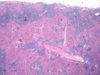

The picture below shows a viral inclusion body for a dog that presented with acute hepatic necrosis and blue eye. What is the likely DDX?

CAV-1 (infectious CN hepatitis)